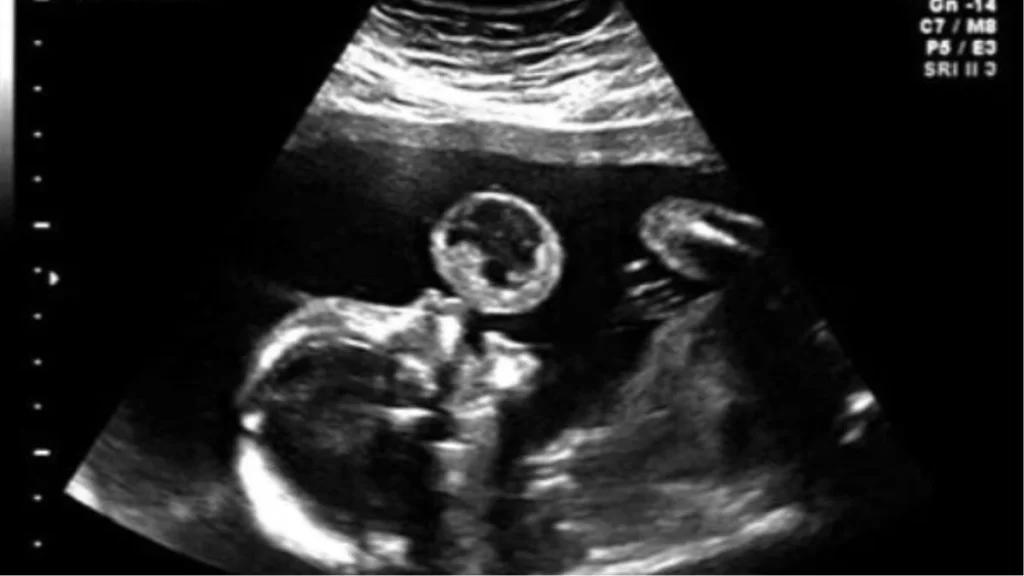

Un’Ecografia Inaspettata

Durante un’ecografia di routine, i medici hanno notato un particolare insolito sul monitor. Sembrava che la bambina, ancora nel grembo materno, stesse formando delle bolle. Un’immagine che inizialmente ha strappato un sorriso a Tammy, ma che ben presto ha rivelato una realtà ben più complessa. La sua piccola, Leyna, era affetta da un raro teratoma orale fetale, un tumore che avrebbe potuto mettere a rischio la sua vita ancor prima della nascita.